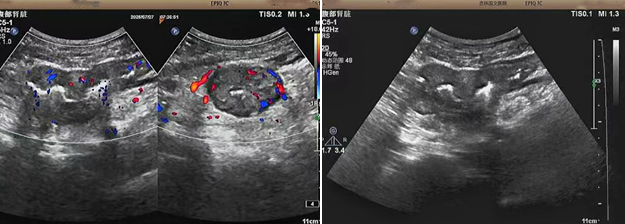

超聲檢查的結(jié)果進一步揭示了病情的細節(jié):下腹部偏左腸壁顯著增厚,原本清晰的層次結(jié)構(gòu)遭到破壞,周圍脂肪間隙變得模糊,網(wǎng)膜回聲也出現(xiàn)增強的現(xiàn)象;同時,腸腔狹窄的情況也得到了確認。經(jīng)過完善的檢查,最終將病變精準定位在乙狀結(jié)腸 - 直腸交界區(qū),并且對病變范圍及周圍浸潤情況做出了評估,這些關(guān)鍵信息為后續(xù)的診療工作提供了重要依據(jù),讓醫(yī)生們能更有針對性地制定治療方案。

我院超聲檢查在此次診療過程中展現(xiàn)出了顯著的技術(shù)亮點。一方面,它能做到 “明察秋毫”,通過高頻探頭可以清晰地顯示腸壁各層結(jié)構(gòu)的變化,為臨床判斷病變性質(zhì)提供了客觀、準確的依據(jù),讓醫(yī)生能更清晰地了解腸道內(nèi)部的病變狀態(tài),另一方面,它實現(xiàn)了 “精準評估”,不僅準確找到了病變的位置,還能全面評估病變對周圍組織的影響,這對于協(xié)助醫(yī)生制定科學合理的治療方案起到了至關(guān)重要的作用,有助于提高治療的有效性和安全性。